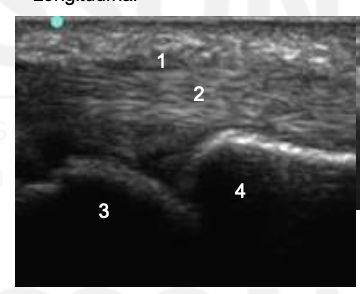

Name 1-4

Thickened A1 pulley

Tendon thickening compared to adjacent tendon. Also note tendon is thicker distal to A1 puley. On dynamic imaging, this impinged onto the A1 pulley.

MCP

Phalanx